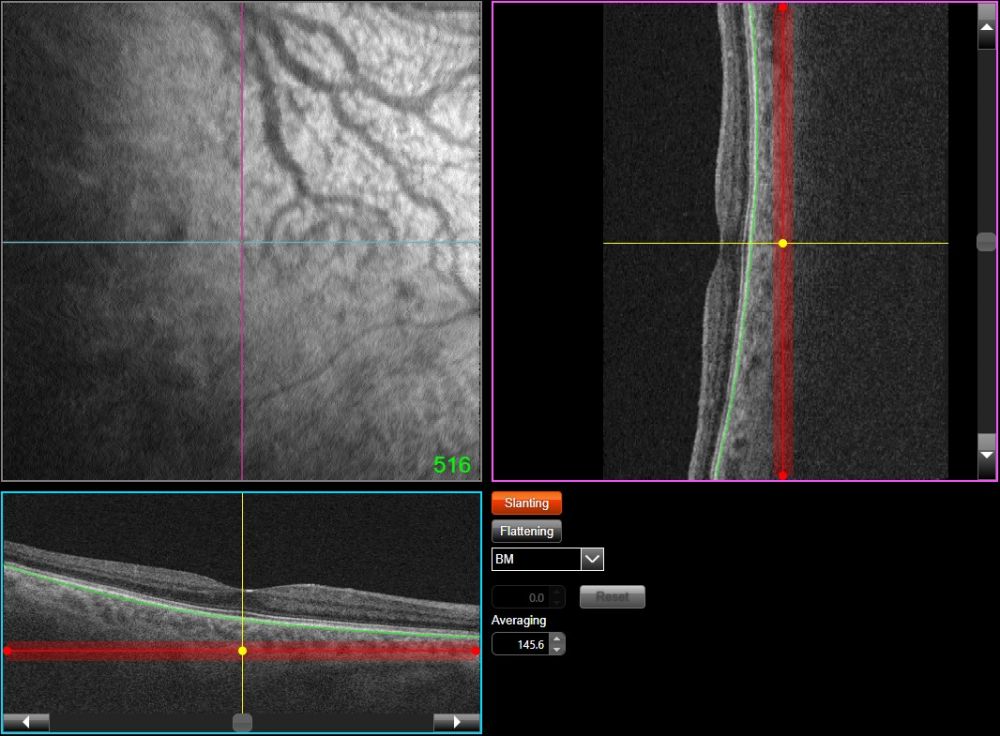

a Initial optical coherence tomography image through the vortex varix ...

Optical coherence tomographical findings in a case of varix of the ...

(PDF) Optical coherence tomographical findings in a case of varix of ...